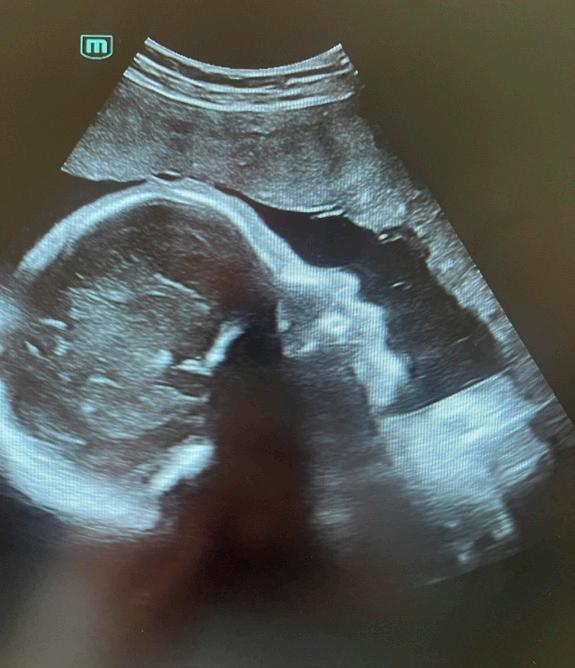

Barnshafandi konum á Suðurnesjum gefst nú í fyrsta sinn tækifæri til að fara í þrívíddarsónar í heimabyggð. Margrét Knútsdóttir, ljósmóðir, hefur látið draum sinn um kaup á sónartæki rætast. „Ég hef endalausan áhuga á öllu sem viðkemur meðgöngu og fæðingu. Ásamt því að sinna ljósmóðurstarfinu til fjölda ára hef ég meðal annars kennt meðgöngujóga í að verða 15 ár og brenn fyrir því að gera meðgöngu kvenna sem ánægjulegasta. Mig hefur því í mörg ár dreymt um að eignast þrívíddarsónar og að geta veitt þessa þjónustu á Suðurnesjum“, segir Margrét ánægð en einnig verður hægt að koma til hennar í svokallaðan kynjasónar eftir 16. viku meðgöngu.

Kíkja á krílið

Meðganga er oft spennandi tími í lífi verðandi foreldra og í sónarskoðun gefst möguleiki á að að kíkja á krílið og tengjast því enn frekar. „Í þrívíddarsónar, sem konur koma í á um sjöunda eða áttunda mánuði meðgöngu, er hægt að sjá krílið hreyfa sig og ef til vill vinka, teygja úr sér eða opna augun. Eitthvað sem getur verið einstök upplifun. Þá get ég einnig útbúið stutt myndband í skoðuninni sem foreldrar fá sent ásamt nokkrum myndum,“ segir Margrét en ítrekar að svona skoðun er ein-

ungis

Notaleg upplifun

Fyrirtæki Margrétar nefnist Lífsins tré og er með aðsetur að Aðalgötu 60, í sama húsnæði og heilsu gæslan Höfða. Hægt er að velja á milli kynjasónar/tvívíddarsónar frá viku sextán og þrívíddarsónar frá viku 26 til 32 á meðgöngu. Skoð unin fer fram í hlýlegu og notalegu umhverfi og mikið lagt upp úr því að gera upplifunina sem besta. Margrét ætlar fyrst um sinn að bjóða upp á tíma síðdegis á virkum dögum en hægt er fá nánari upp lýsingar og panta tíma í gegnum vefsíðuna hennar

til gamans gerð og ekki um fósturgreiningu að ræða.